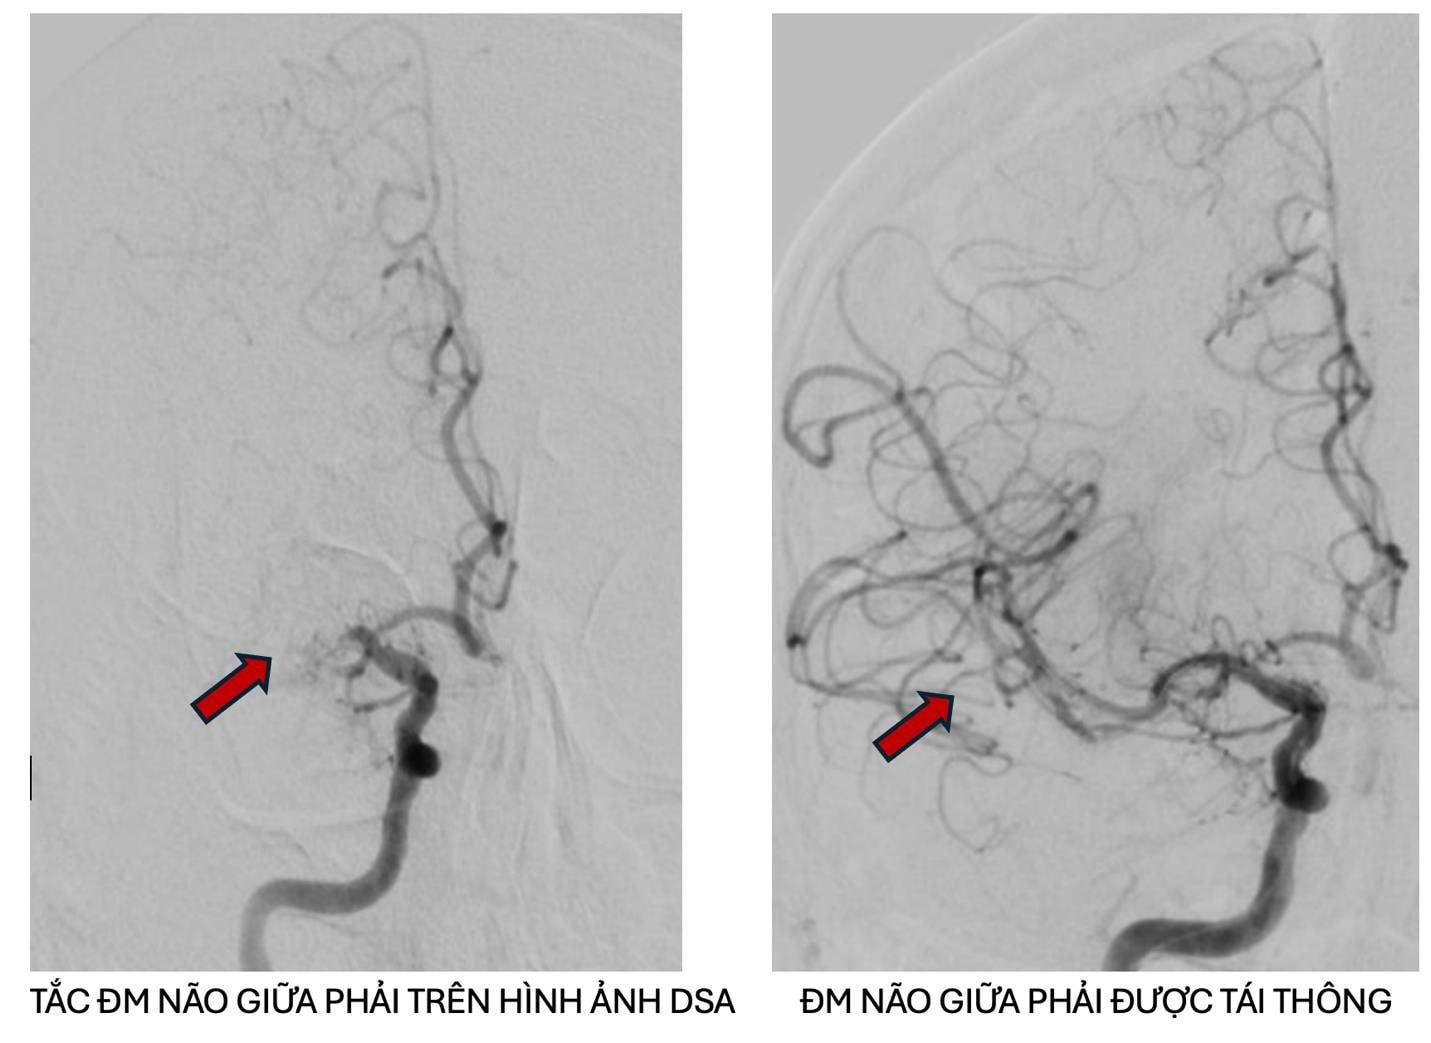

Trên kết quả kiểm tra hình ảnh, bác sĩ chẩn đoán bệnh nhân bị tắc động mạch não giữa bên phải trên nền hẹp nặng do xơ vữa động mạch. Đây là dạng đột quỵ nguy hiểm, có thể để lại di chứng nặng nề hoặc tử vong nếu không được xử lý khẩn cấp. Sau khi kiểm tra chuyên sâu, các bác sĩ đã chỉ định can thiệp lấy huyết khối khẩn cấp cho người bệnh. Sau khi can thiệp, hình ảnh chụp động mạch não cho thấy dòng máu đã được tái thông hoàn toàn, bảo tồn được vùng mô não còn sống.